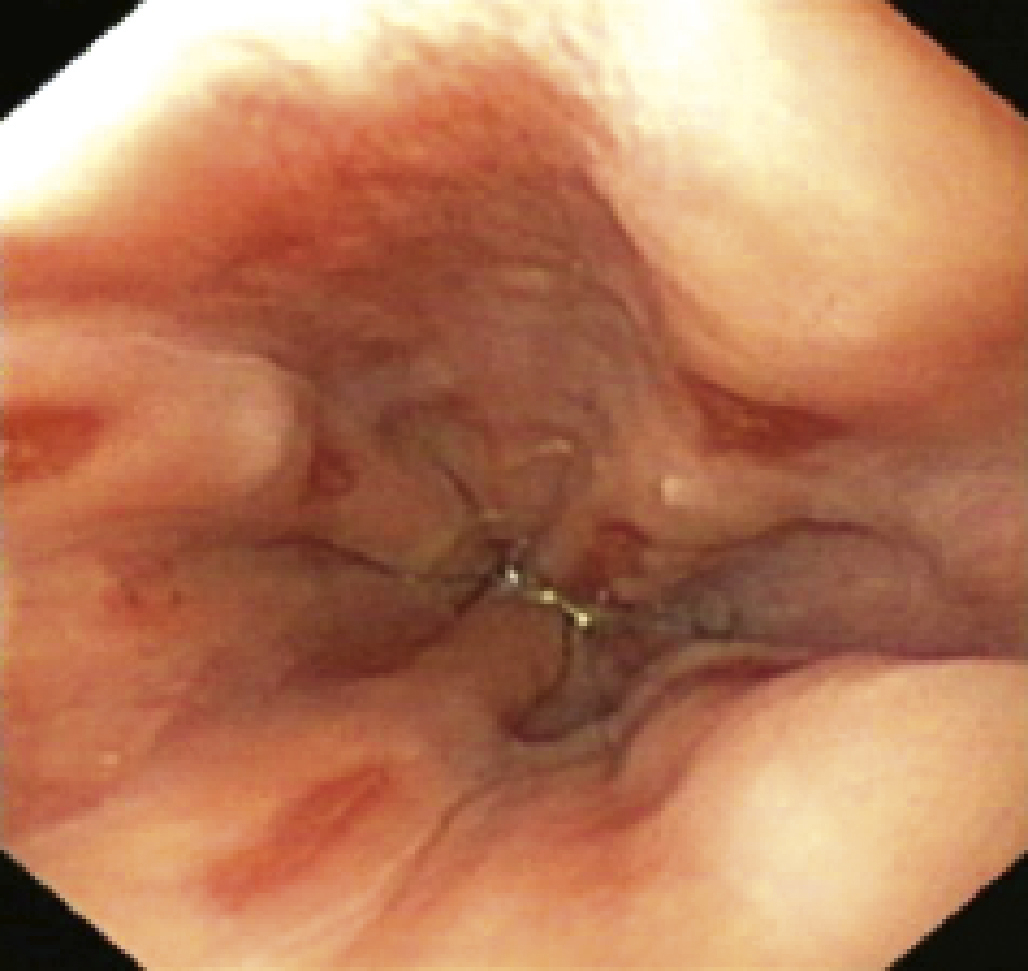

• douleur rétrosternale lors de l’alimentation, voire hématémèse et anémie, qui font évoquer une œsophagite (fig. 2) ;